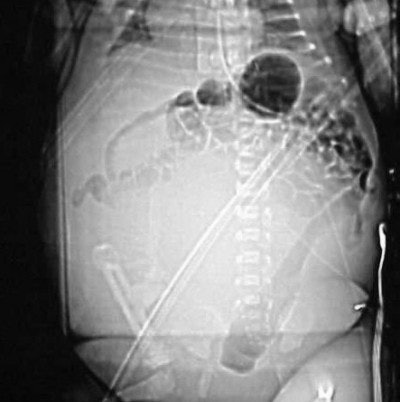

Case 2: The patient is a newborn girl with a large soft-tissue mass extending from her buttocks through her thighs. The scout AP image (Figure CT 12) shows an extensive, rounded soft-tissue mass.

It is uncommon to use contrast in an infant less than six months old because their kidneys are not yet fully developed. In this case, doctors decided that the benefits were worth the risk of harm, so I used 4 cc of Visipaque (iodixanol, GE Healthcare Bio-Sciences, Buckinghamshire, U.K.) hand-injected through a 24-gauge angiocath with a 20-second delay.

Images (Figures CT 13 and CT 14) show a large, enhancing, soft-tissue mass extending from the buttocks, past the labial folds, and into the thighs. She was diagnosed with a rhabdomyosarcoma that was successfully excised.